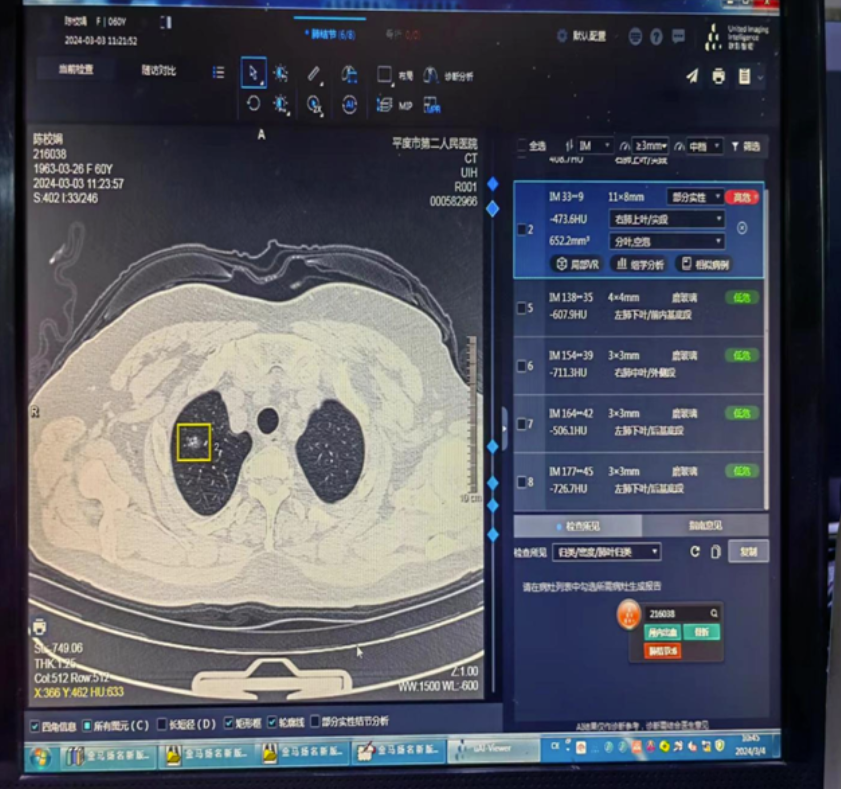

鉴于以上情况,该院医学影像科在院部大力支持下成功引进并安装肺结节AI软件,用于广大患者及特殊人群就诊检查及常规体检的需求。

低剂量CT筛查发现的肺结节,假阳性率较高;在国家肺部筛查试验研究中,对于直径≥4 mm的肺结节,经过3轮低剂量CT筛查后,肺结节诊断的假阳性率高达96.4%。应用人工智能辅助进行肺结节诊断,能高效判别出肺小结节和非结节,从而提高肺结节检出率。有研究证实,在CT阅片过程中,应用人工智能辅助技术进行肺结节的识别,其灵敏度高达96.7%,显著优于影像科医生的78.1%,并且拥有更快的读片速度,提示其在肺癌筛查中具有重要的临床价值和广泛的应用前景

应用人工智能辅助进行肺结节良恶性鉴别诊断,可能具备以下优势:一方面,人工智能辅助影像学诊断可以快速给出肺结节的良恶性判断及其恶性风险分级,提高诊断效率的同时,还能突显肺结节图像中的可疑征象,并实时呈现给临床医生,为肺结节的分类诊断提供重要参考依据,从而有利于降低误诊率;另一方面,人工智能还可用于计算肺结节的体积,相比于手动测量,该方式具有高度的可重复性,优势明显,并可通过比较多次影像数据估计肺结节体积的倍增时间,可以协助判断结节的生长情况,进行良恶性鉴别。